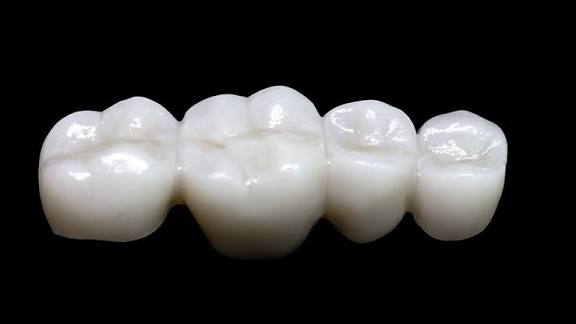

歯の治療でジルコニアにするか悩む

自分も3本ジルコニアにしたけど20年は持つし年数で割れば1本7万くらい安いもんだ

神経残ってるならジルコニアの方がいいよね

銀歯は染みが怖いし

あと地味に金属アレルギーになったらも怖いよね

526/01/16(金)14:28:16No.1392954543そうだねx9

>見分けはつかないけど気軽に割れるぜ

セラミックは歯より硬度が低いから削れる分寿命が短い

ジルコニアは歯より少し硬度が上で数十年持つ

今はさらにジルコニアの複合素材のe-maxもある

奥歯に一番安い単色のジルコニアぶち込んだ

いいぞジルコニアは

ジルコニアは強度ありすぎて噛み合わせの歯側が痛むよって言われて数年だけど今のところ全然大丈夫だな